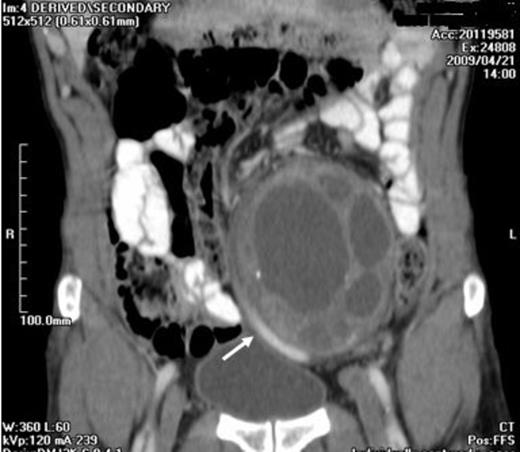

A 57-year-old man presented with a 3-month history of vague abdominal pain. There was no family history of RSs. The bowel and bladder habits were normal. On physical examination, there was a large, firm, non-tender palpable abdominal mass behind the umbilicus. There was no palpable lymphadenopathy. All vital signs, the chest X-ray, haemogram, biochemical analysis and tumor markers were normal. Computed tomography (CT) confirmed a 9×9x12 cm large, heterogeneous, multilocular, cystic mass with a thick wall and irregular septum in the left retroperitoneal area (Figure 1).

A CT image showing a heterogeneous, multilocular, cystic mass which is localized to the anteromedial aspect of the psoas muscle begining from the left L5 - S1 intervertebral foramina

It was localised to the anteromedial aspect of the psoas muscle extending from L4 to S1. The left common iliac, external and internal iliac arteries were displaced medially and both the external and internal iliac veins were dilated. The common iliac vein was not separated from the mass. (Figure 2)